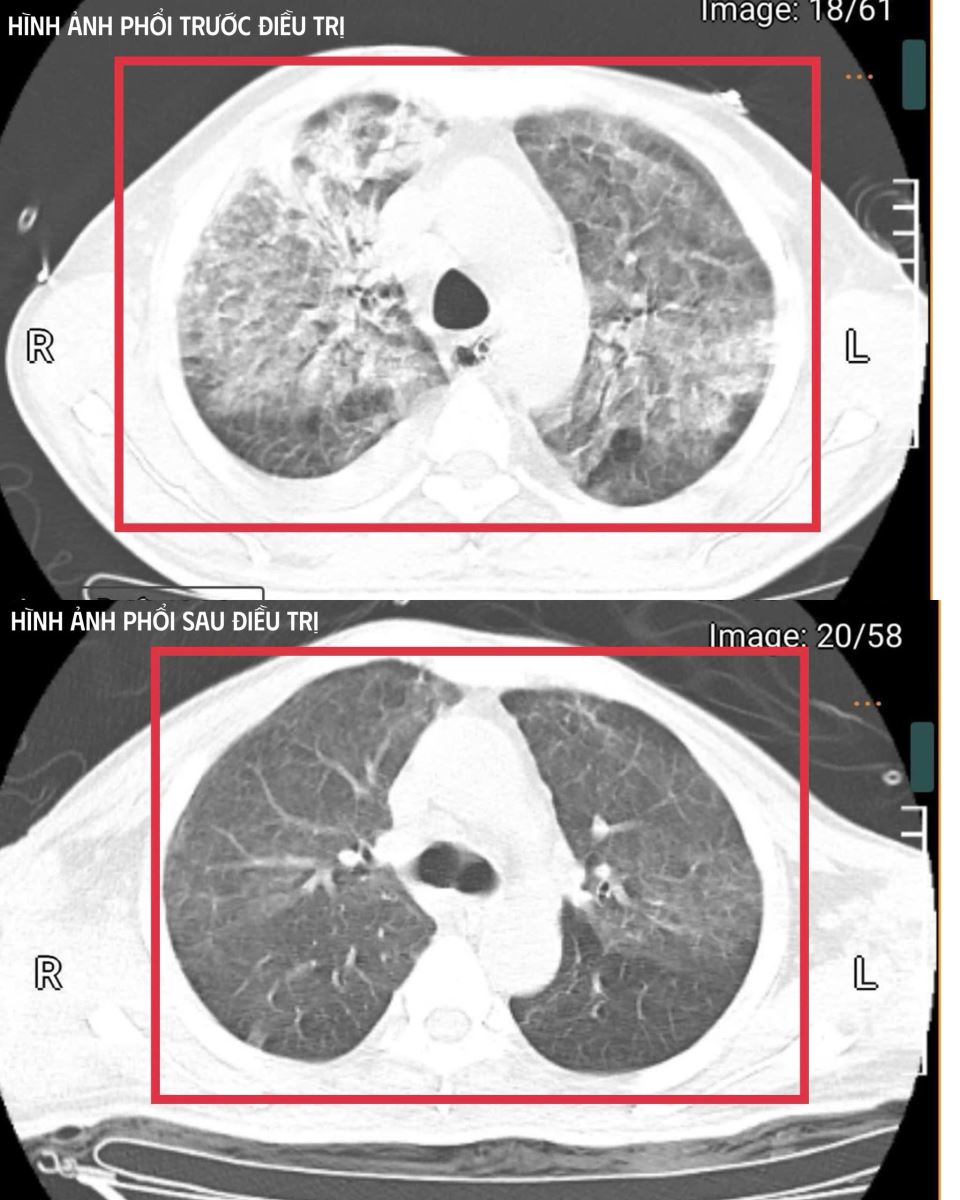

Hình ảnh chụp phổi của bệnh nhân mắc Whitmore.

Sau ba tuần điều trị, bệnh nhân đã hồi phục hoàn toàn: tỉnh táo, tự thở khí phòng, huyết áp ổn định, cơ lực chi trên đạt 5/5, chi dưới 4/5.

Bệnh nhân được cai máy thở (qua mở khí quản), tập hô hấp tự nhiên và phục hồi vận động. Sau ba tuần điều trị, bệnh nhân đã hồi phục hoàn toàn: tỉnh táo, tự thở khí phòng, huyết áp ổn định, cơ lực chi trên đạt 5/5, chi dưới 4/5. Bệnh nhân được xuất viện và tiếp tục theo dõi ngoại trú.